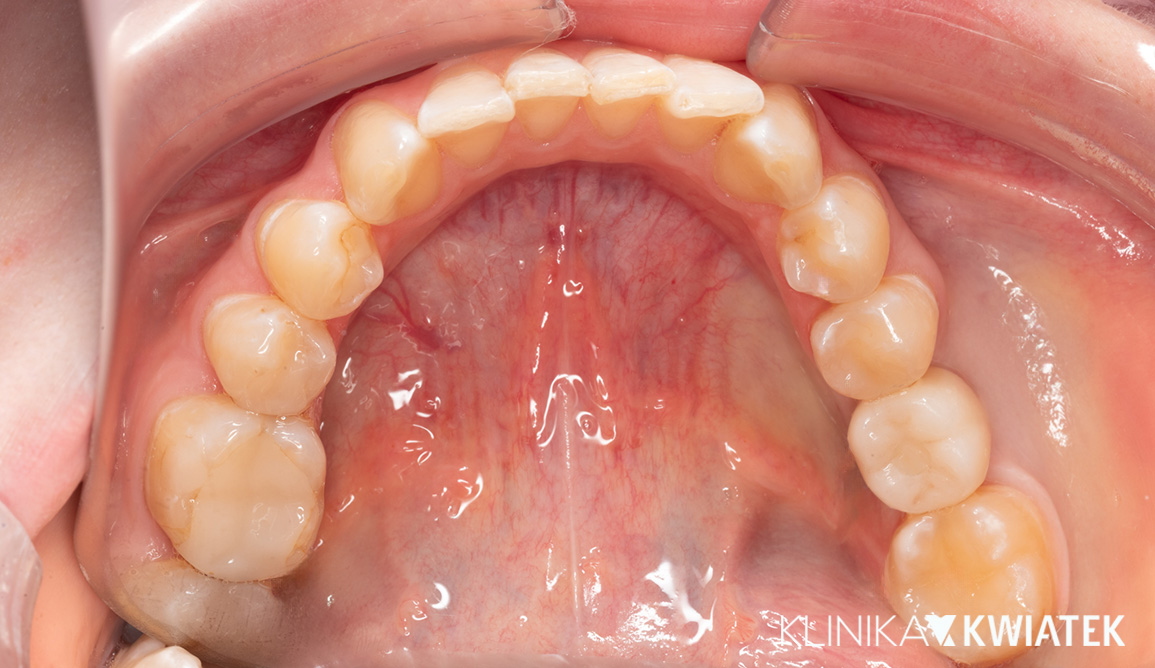

Pacjentka zgłosiła się z wadą zgryzu, licznymi ubytkami i utraconymi zębami trzonowymi, co powodowało trudności w żuciu i estetyczne niezadowolenie. Leczenie obejmowało ekstrakcje, ortodoncję, implantację oraz kompleksową rekonstrukcję protetyczną. Po kilkunastu miesiącach terapii Pacjentka odzyskała pełną funkcję zgryzu i piękny, harmonijny uśmiech.